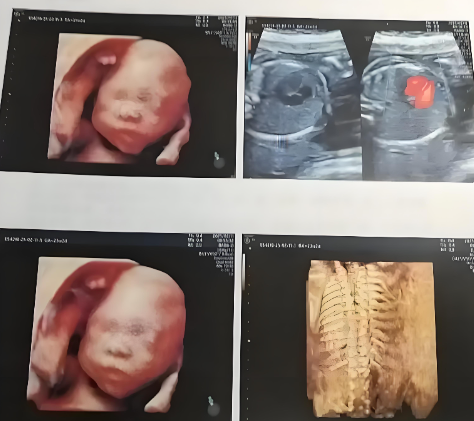

大排畸检查通常指孕中期系统性超声检查,多在孕20至24周进行,部分医院会建议在22至26周完成。此阶段胎儿大小适中、羊水量充足、活动空间较大,超声成像更清晰,便于医生全面观察器官结构。

核心目标 包括:排查胎儿重大结构畸形(如心脏缺陷、神经管异常、肢体缺失等),评估生长发育指标(双顶径、股骨长、腹围等),确认胎盘位置与羊水量是否正常。这是保障母婴健康的关键筛查,远早于或晚于此时段,成像质量可能下降,漏诊风险增加。